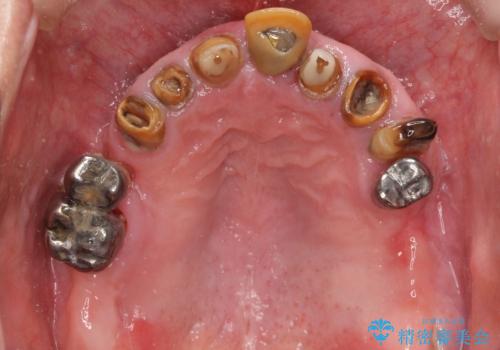

- 歯がぐらぐらで咬めないことを主訴に来院された患者様です。

他院では上顎骨が薄いためインプラントできないと言われたとのことでした。

精査したところ、歯周病に罹患した歯を長年放置したことから骨吸収が進行し、上顎骨の厚みはとても薄くなっていました。